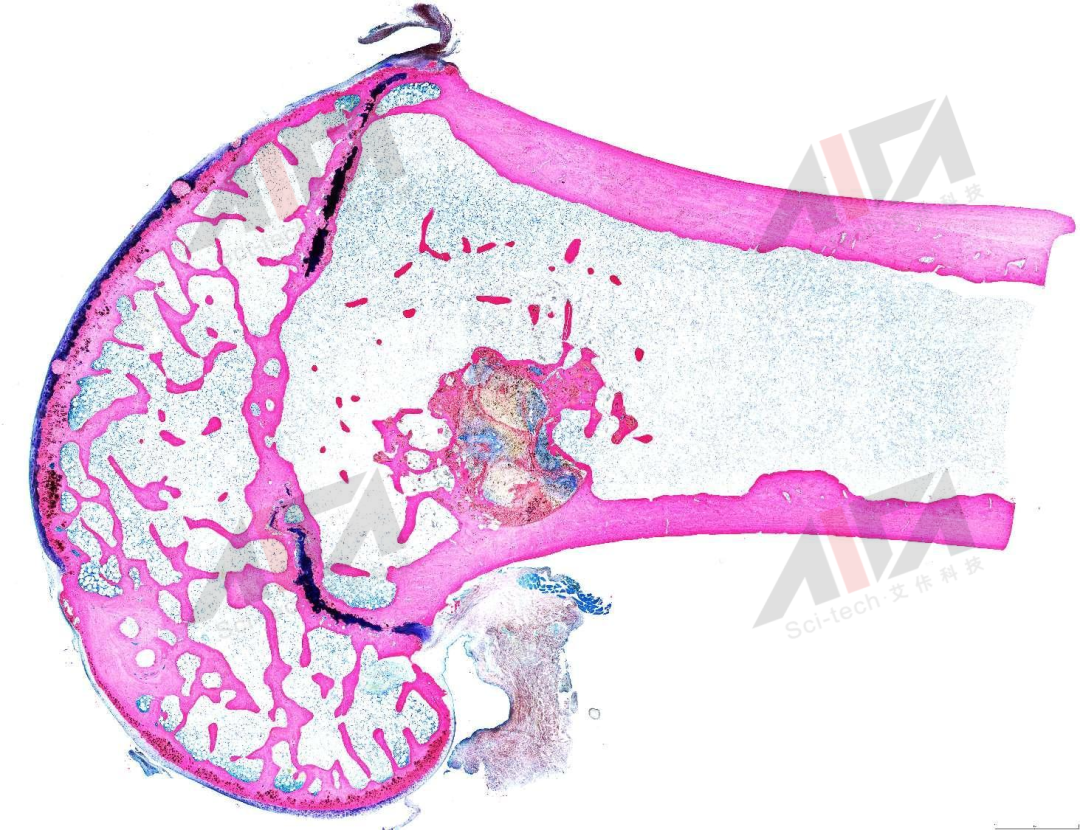

图片

硬组织切磨片-VK染色

硬组织切磨片-Masson-goldner染色